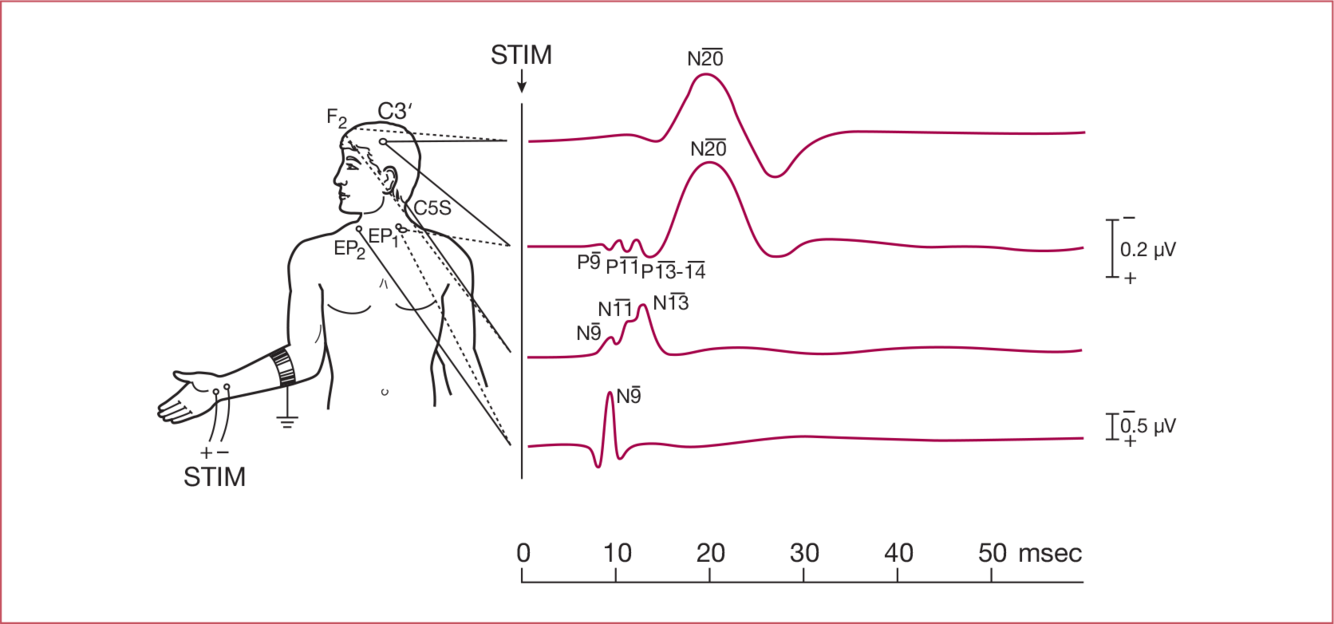

How long does it take median nerve stimulation at the wrist to reach Erb’s point? How long to reach the cortex?

9 msec and 20 msec respectively